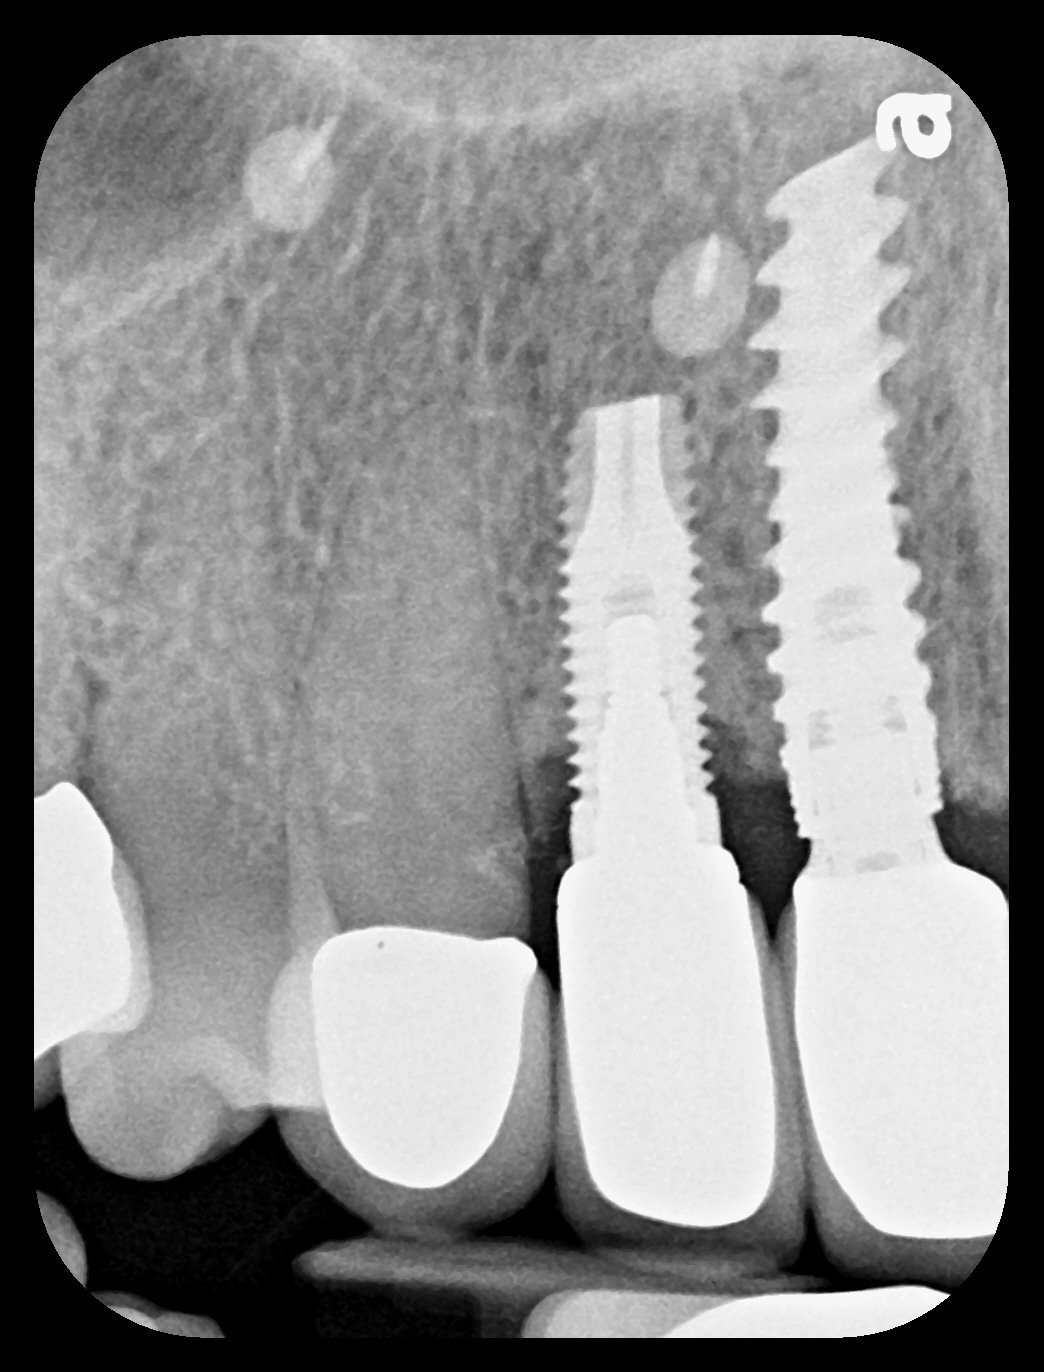

Fig 5. Radiograph 6 years after peri-implantitis repair (2014).

Figure 5